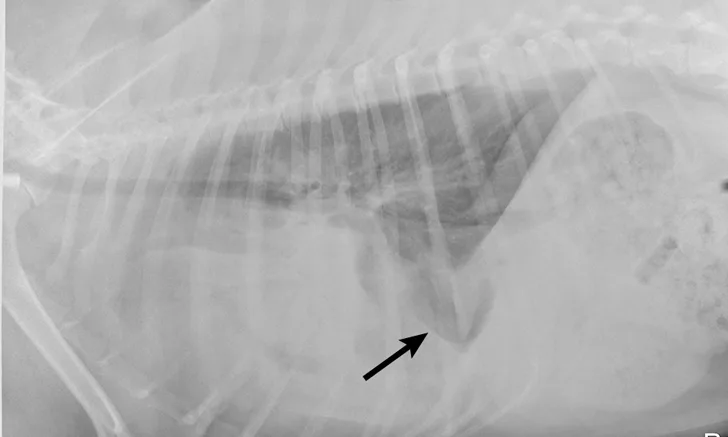

Radiographs obtained after thoracocentesis demonstrated improved pleural effusion and consolidation of the left middle lung lobe (Figure 3). Based on the soft tissue bulge near the hilum and the air bronchocram extending cranially, the primary differential was lung lobe torsion (LLT). Other considerations included pulmonary mass, abscess, or granuloma.

FIGURE 3A

Right lateral (A) and ventrodorsal (B) thoracic radiographs obtained after thoracocentesis showing improvement in pleural effusion with a persistent soft tissue opacity in the left mid-to-cranial thorax. An air bronchogram is seen extending cranially from the hilus (arrowhead) where a subtle bulge (arrow) is present.